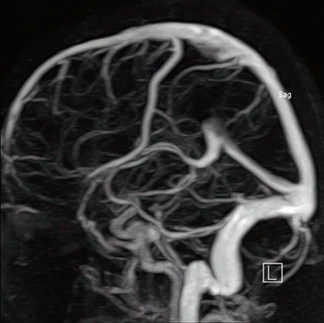

Диагностика магнитно-резонансная ангиография сосудов головного мозга производится при подозрении на тромбофлебит сигмовидного синуса.

- МРТ ангиографии сосудов головного мозга с контрастированием

Тромбоз сигмовидного синуса нужно дифференцировать от врождённой атрезии (недоразвития) синуса. В случае нормально развитой выемки для сигмовидного синуса на КТ головного мозга (рисунок А), можно предполагать синус-тромбоз справа. В случае недоразвитой выемки для сигмовидного синуса (рисунок В), можно предполагать врождённую атрезию (недоразвитие) правого сигмовидного синуса.